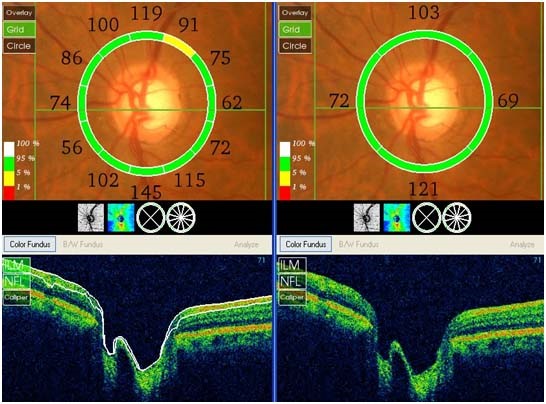

Debido a esto, es muy importante el diagnóstico y tratamiento en estadios iniciales, cuando el paciente todavía no presenta síntomas. Esto puede llevarse a cabo en consultas de cribado o revisiones, recomendadas a partir de los 40 años, especialmente si existen antecedentes familiares. En dichas consultas, se realizará la medición de la presión intraocular y la evaluación del nervio óptico mediante examen de fondo de ojo, el análisis de las fibras nerviosas mediante tomografía de coherencia óptica (OCT) y la evaluación del campo visual.

OCT de nervio óptico

Nervio óptico glaucomatoso